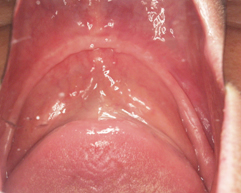

通常虫歯になった部分は、大きく削り取って被せ物をする、という治療が一般的です。 また、神経にまで達してしまった虫歯や神経の近くまで進行している虫歯は、神経を抜いてしまう、という治療が一般的です。   […]